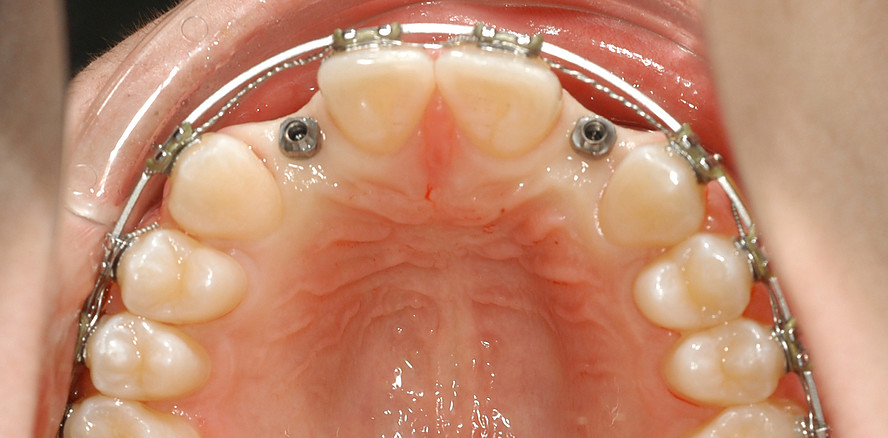

Ein 14-jähriger Patient wurde bei Aplasie der beiden oberen seitlichen Schneidezähne mit dem Ziel der beidseitigen Lückenöffnung kieferorthopädisch therapiert (Abb. 1a+b). Zum Ende der kieferorthopädischen Behandlung wurden zwei Miniimplantate in Regio 2er als temporärer Zahnersatz inseriert (Benefit System, PSM, 2 x 13 mm, Abb. 2a+b). Nach Abdrucknahme wurden Kronen auf den Peek-Abutments modelliert und diese mit Kunststoff auf die Abutments geklebt (Abb. 3a–d). In den Abbildungen 3 und 4 sind die klinischen und röntgenologischen Nachkontrollen innerhalb der nächsten achteinhalb Jahre dokumentiert. Man erkennt einen sowohl in der Höhe als auch in bukkopalatinalen Breite verbleibenden gesunden Knochen ohne Anzeichen einer Atrophie. Im Alter von 23 Jahren wurden die definitiven Implantate ohne die Notwendigkeit einer Augmentation eingesetzt (Abb. 5) und nach Einheilung prothetisch versorgt (Abb. 6a–e und Abb. 7a–c).